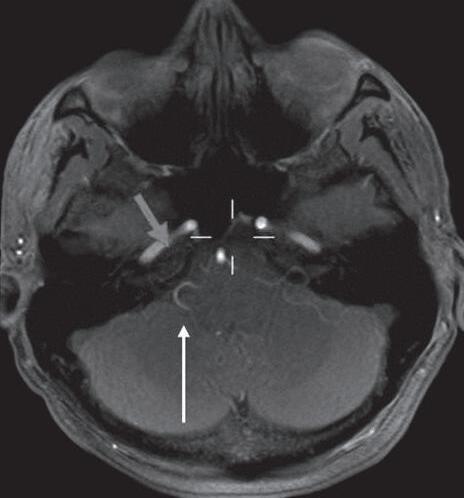

A angio TC e a angio RNM são importantes para o diagnóstico de aneurismas cerebrais, malformações arteriovenosas, estenoses e oclusões vasculares, trombose venosa cerebral, bem como conflitos neurovasculares. Além disso, podem ser utilizadas para o planejamento de procedimentos cirúrgicos, permitindo a visualização da anatomia dos vasos sanguíneos cerebrais antes da cirurgia. A angio RNM permite melhor acurácia e definição das estruturas vasculares intracranianas, sendo indicada em investigação de pequenos aneurismas e conflitos neurovasculares. A escolha entre os métodos abrange desde a suspeita clínica, urgência do diagnóstico e limitações relacionadas ao paciente, sendo a angio TC um método de menor custo e maior disponibilidade, enquanto a RNM é um exame com maior tempo para aquisição das imagens e contraindicações mais amplas, devendo-se avaliar previamente a compatibilidade de dispositivos gerais e materiais metálicos com o aparelho de RNM (Figs. 1-22 a 1-24).

Para a avaliação de conflitos neurovasculares as sequências volumétricas (FIESTA, CISS, BALANCE, SPACE, de acordo com os fabricantes) possibilitam o diagnóstico na maioria dos casos, mas podem ser associadas às imagens de angio RNM em casos duvidosos.

Fig. 1-23. Paragangliomas jugulotimpânicos à esquerda e carotídeos bilaterais. RNM coronal T1 com supressão de gordura pós-Gd (a): lesão expansiva hipervascularizada no forame jugular esquerdo, com extensão à cavidade timpânica. Angio RNM sequência TRICKS pós-Gd (b): paraganglioma jugulotimpânico à esquerda (seta curta) e carotídeos (setas longas), individualizados na angio RNM, com enchimento precoce pelo agente paramagnético.

Fig. 1-24. Conflito neurovascular da P.I.C.A. com o VIII nervo craniano direito no trajeto cisternal. Sequência volumétrica axial FIESTA (a): P.I.C.A. (seta vermelha curta) em contato com o VIII nervo craniano junto à zona de entrada no tronco cerebral (seta branca longa); angio RNM (3DTOF) (b) P.I.C.A. (seta amarela) projetando-se cranial e lateralmente no trajeto do VIII nervo; imagem de aquisição da angio RNM (c) P.I.C.A. projetando-se junto ao VIII nervo direito (seta branca longa); VIII (seta vermelha curta).